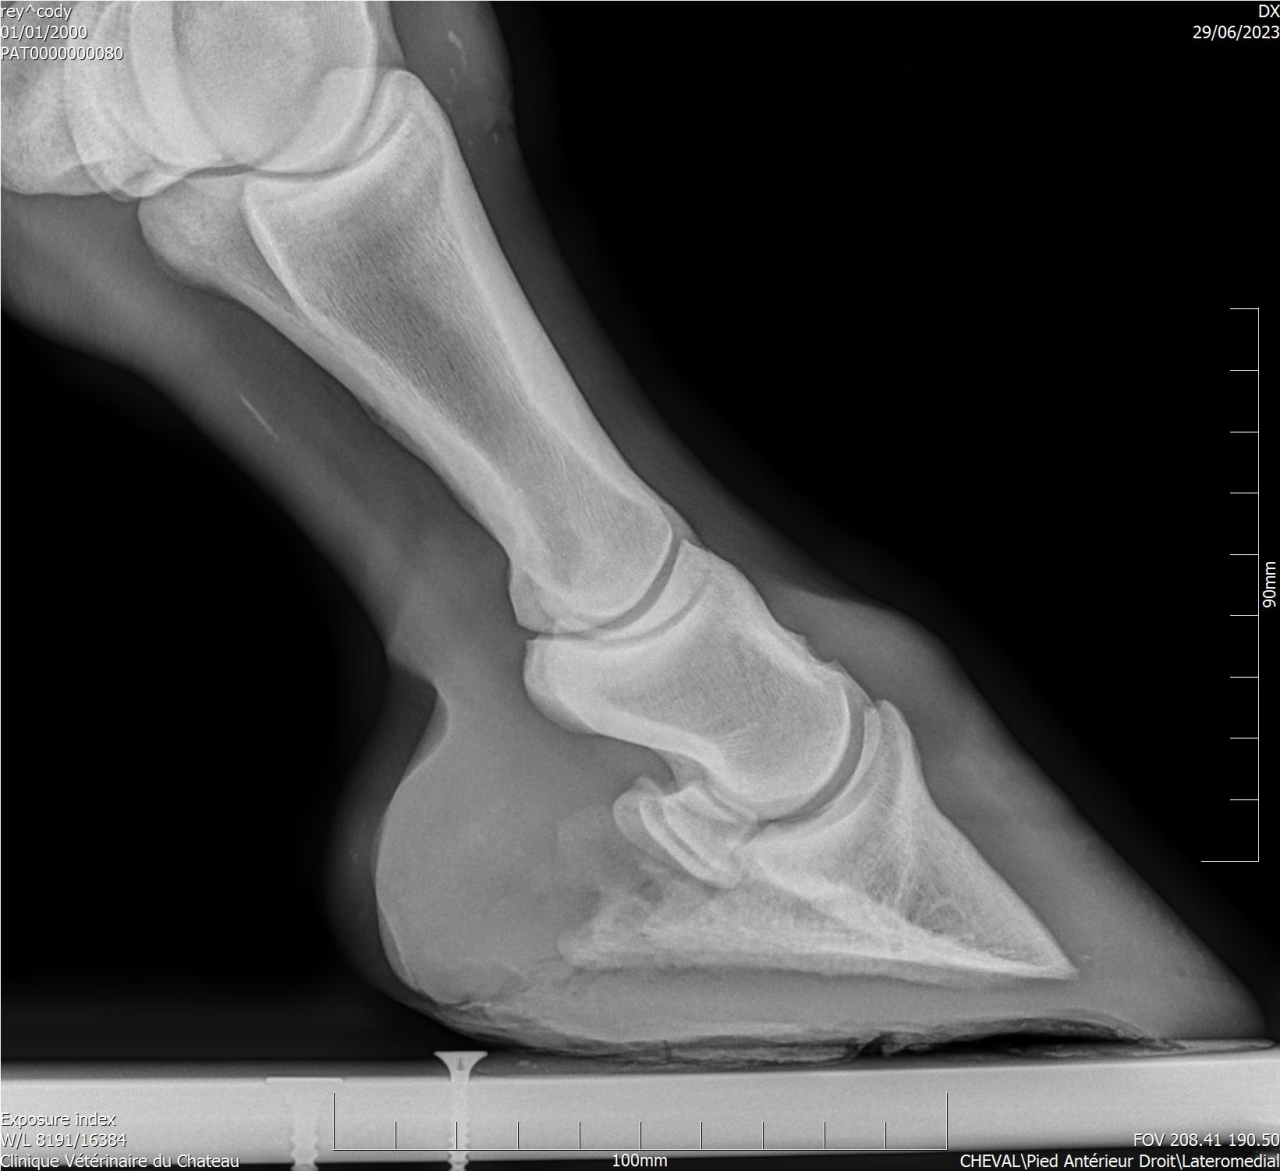

| Dire merci | Je fais un sujet à part pour donner des nouvelles ![]() J’ai fait passer un autre véto pour un 2ème avis. Au début il pensait à un abcès très profond, emplacement détecté avec la pince à sonder. Il a ensuite fait des radios : si j’ai bien compris, la 3ème phalange appuie sur la sole Il y a également de l’arthrose ... Le traitement pour le moment : anti inflammatoires et hipposandales en attendant de pouvoir referrer, et changer de maréchal ferrant. Apparemment il existerait un traitement au laser, le véto va se renseigner. Cody a fait une fourbure l’année dernière, des radios ont été faites à ce moment. J’ai aussi refait des radios de contrôle cette année, il restait une légère bascule de P3. |

| Dire merci | Il y a quand même de jolies bascules, il doit pas être bien c'est sûre. Les degrés de bascule t'ont été donnés? Pour moi il y a urgence à trouver un bon maréchal, qui va travailler avec les radios, mais ça va mettre plusieurs mois à "rentrer dans l'ordre" si pas d'autres crises inflammatoires et nouvelles bascules, ça se compte en plusieurs mois voir année. Et malheureusement une surveillance constante. |

| Dire merci | J'ai eu le collègue du véto au téléphone : pas de risque immédiat que la phalange perce la sole il reste 1 cm. La 3ème phalange appuie sur la sole, il y a nécrose. La pointe ne risque pas de casser. Je viens de commander 2 hipposandales Cloud. Il faut que je trouve quelqu'un pour déferrer Cody et éventuellement parer l’autre antérieur. Message édité le 22/11/24 à 20:31 |

| Dire merci | Voici les dernières radios :![]() ![]() ![]() |